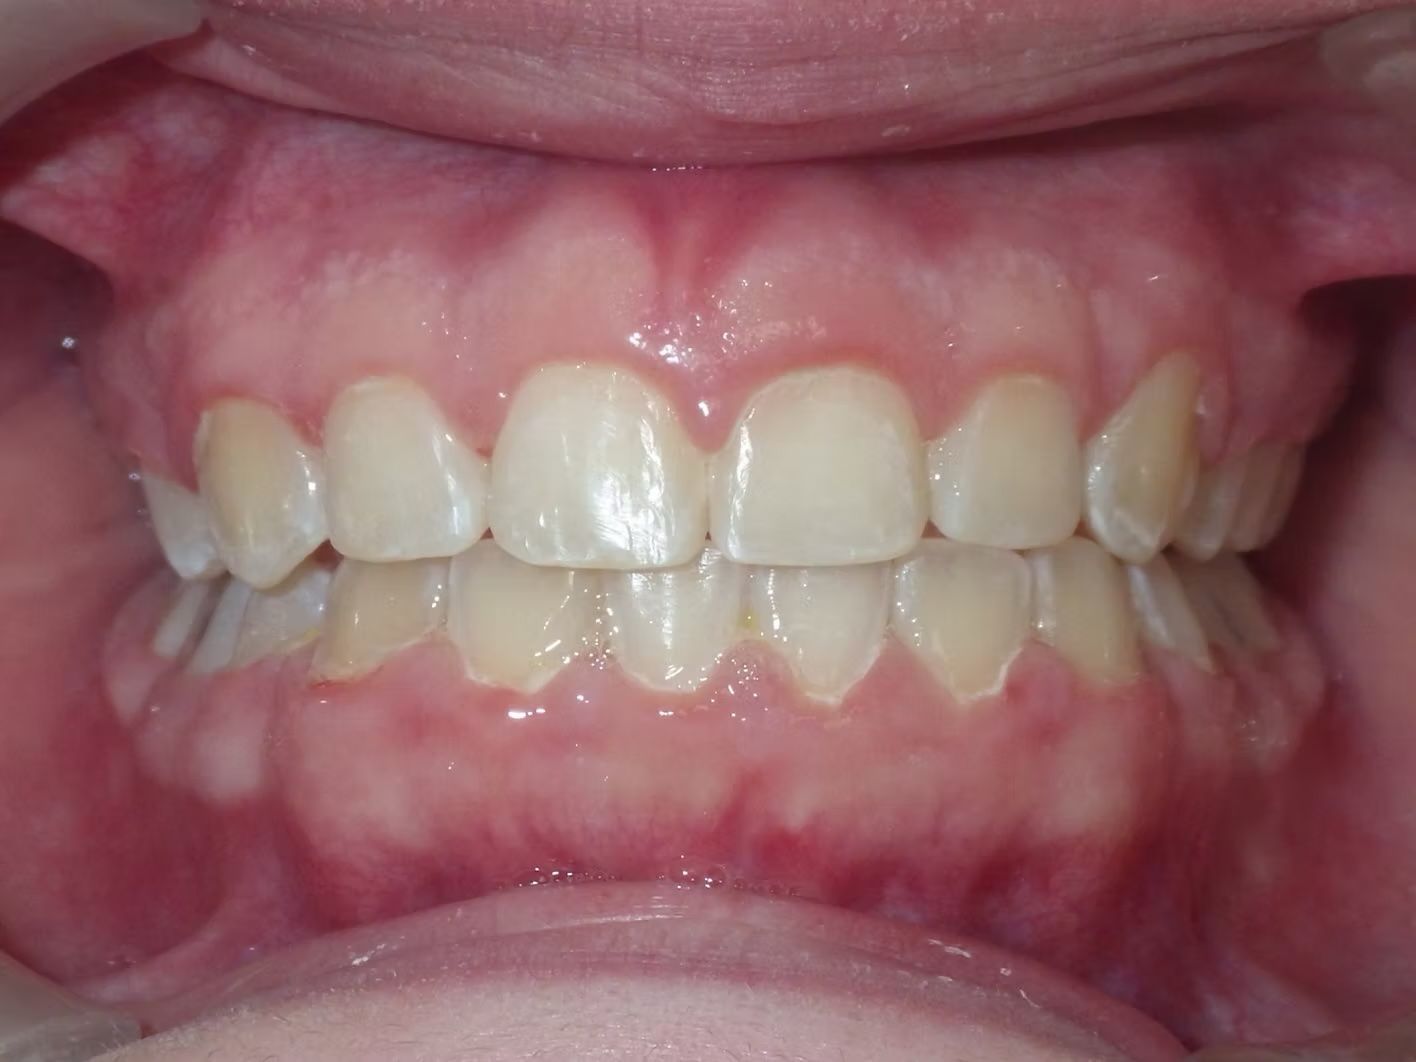

Johntavious

Johntavious didn't like that one of his lower teeth was set behind the rest. He went to many orthodontists who told him to extract the tooth or multiple teeth to correct the alignment. Johntavious and his parents didn't want to go that route and wanted to try to align the teeth without the extraction. Dr. Bret was able to successfully straighten the upper and lower teeth - fit the tooth that was back into the dental arch and make Johntavious and his parents really happy.